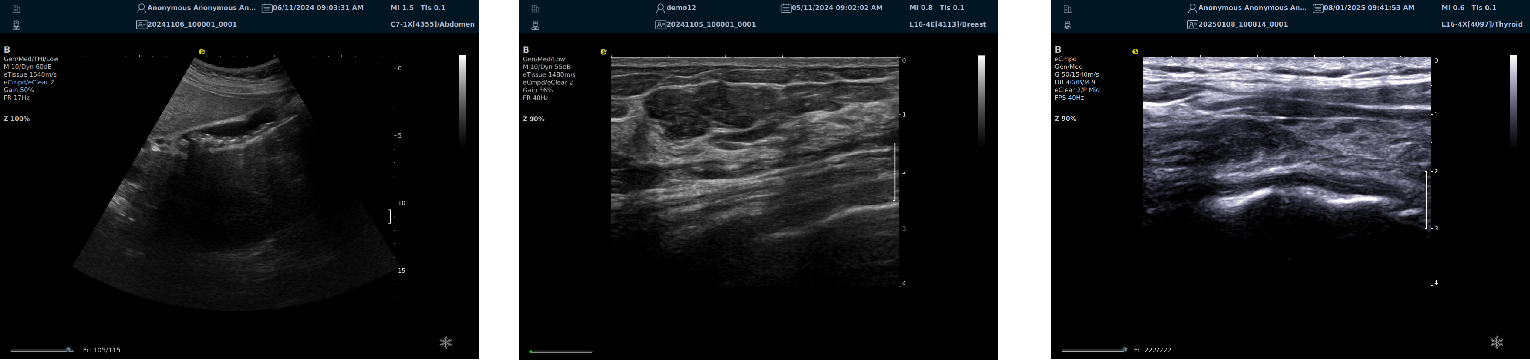

优异的二维图像

image.png

平面波超微细血流显像

能够提供更多真实的组织细小及末梢血管的血流信息,直观的观察组织内部的血管架构及血流形态的情况,提供临床更多有价值的诊断信息。

临床应用:

肿瘤鉴别诊断(肝脏、肾脏、甲状腺、乳腺、  涎腺等)

淋巴结评价(炎症、肿瘤)

肌骨系统临床诊断和疗效监测(关节、滑膜、韧带、肌肉炎症、 损伤等)

斑块内新生血管评估

超声介入术前进针方案提供血流参考信息

超声介入术后疗效评估